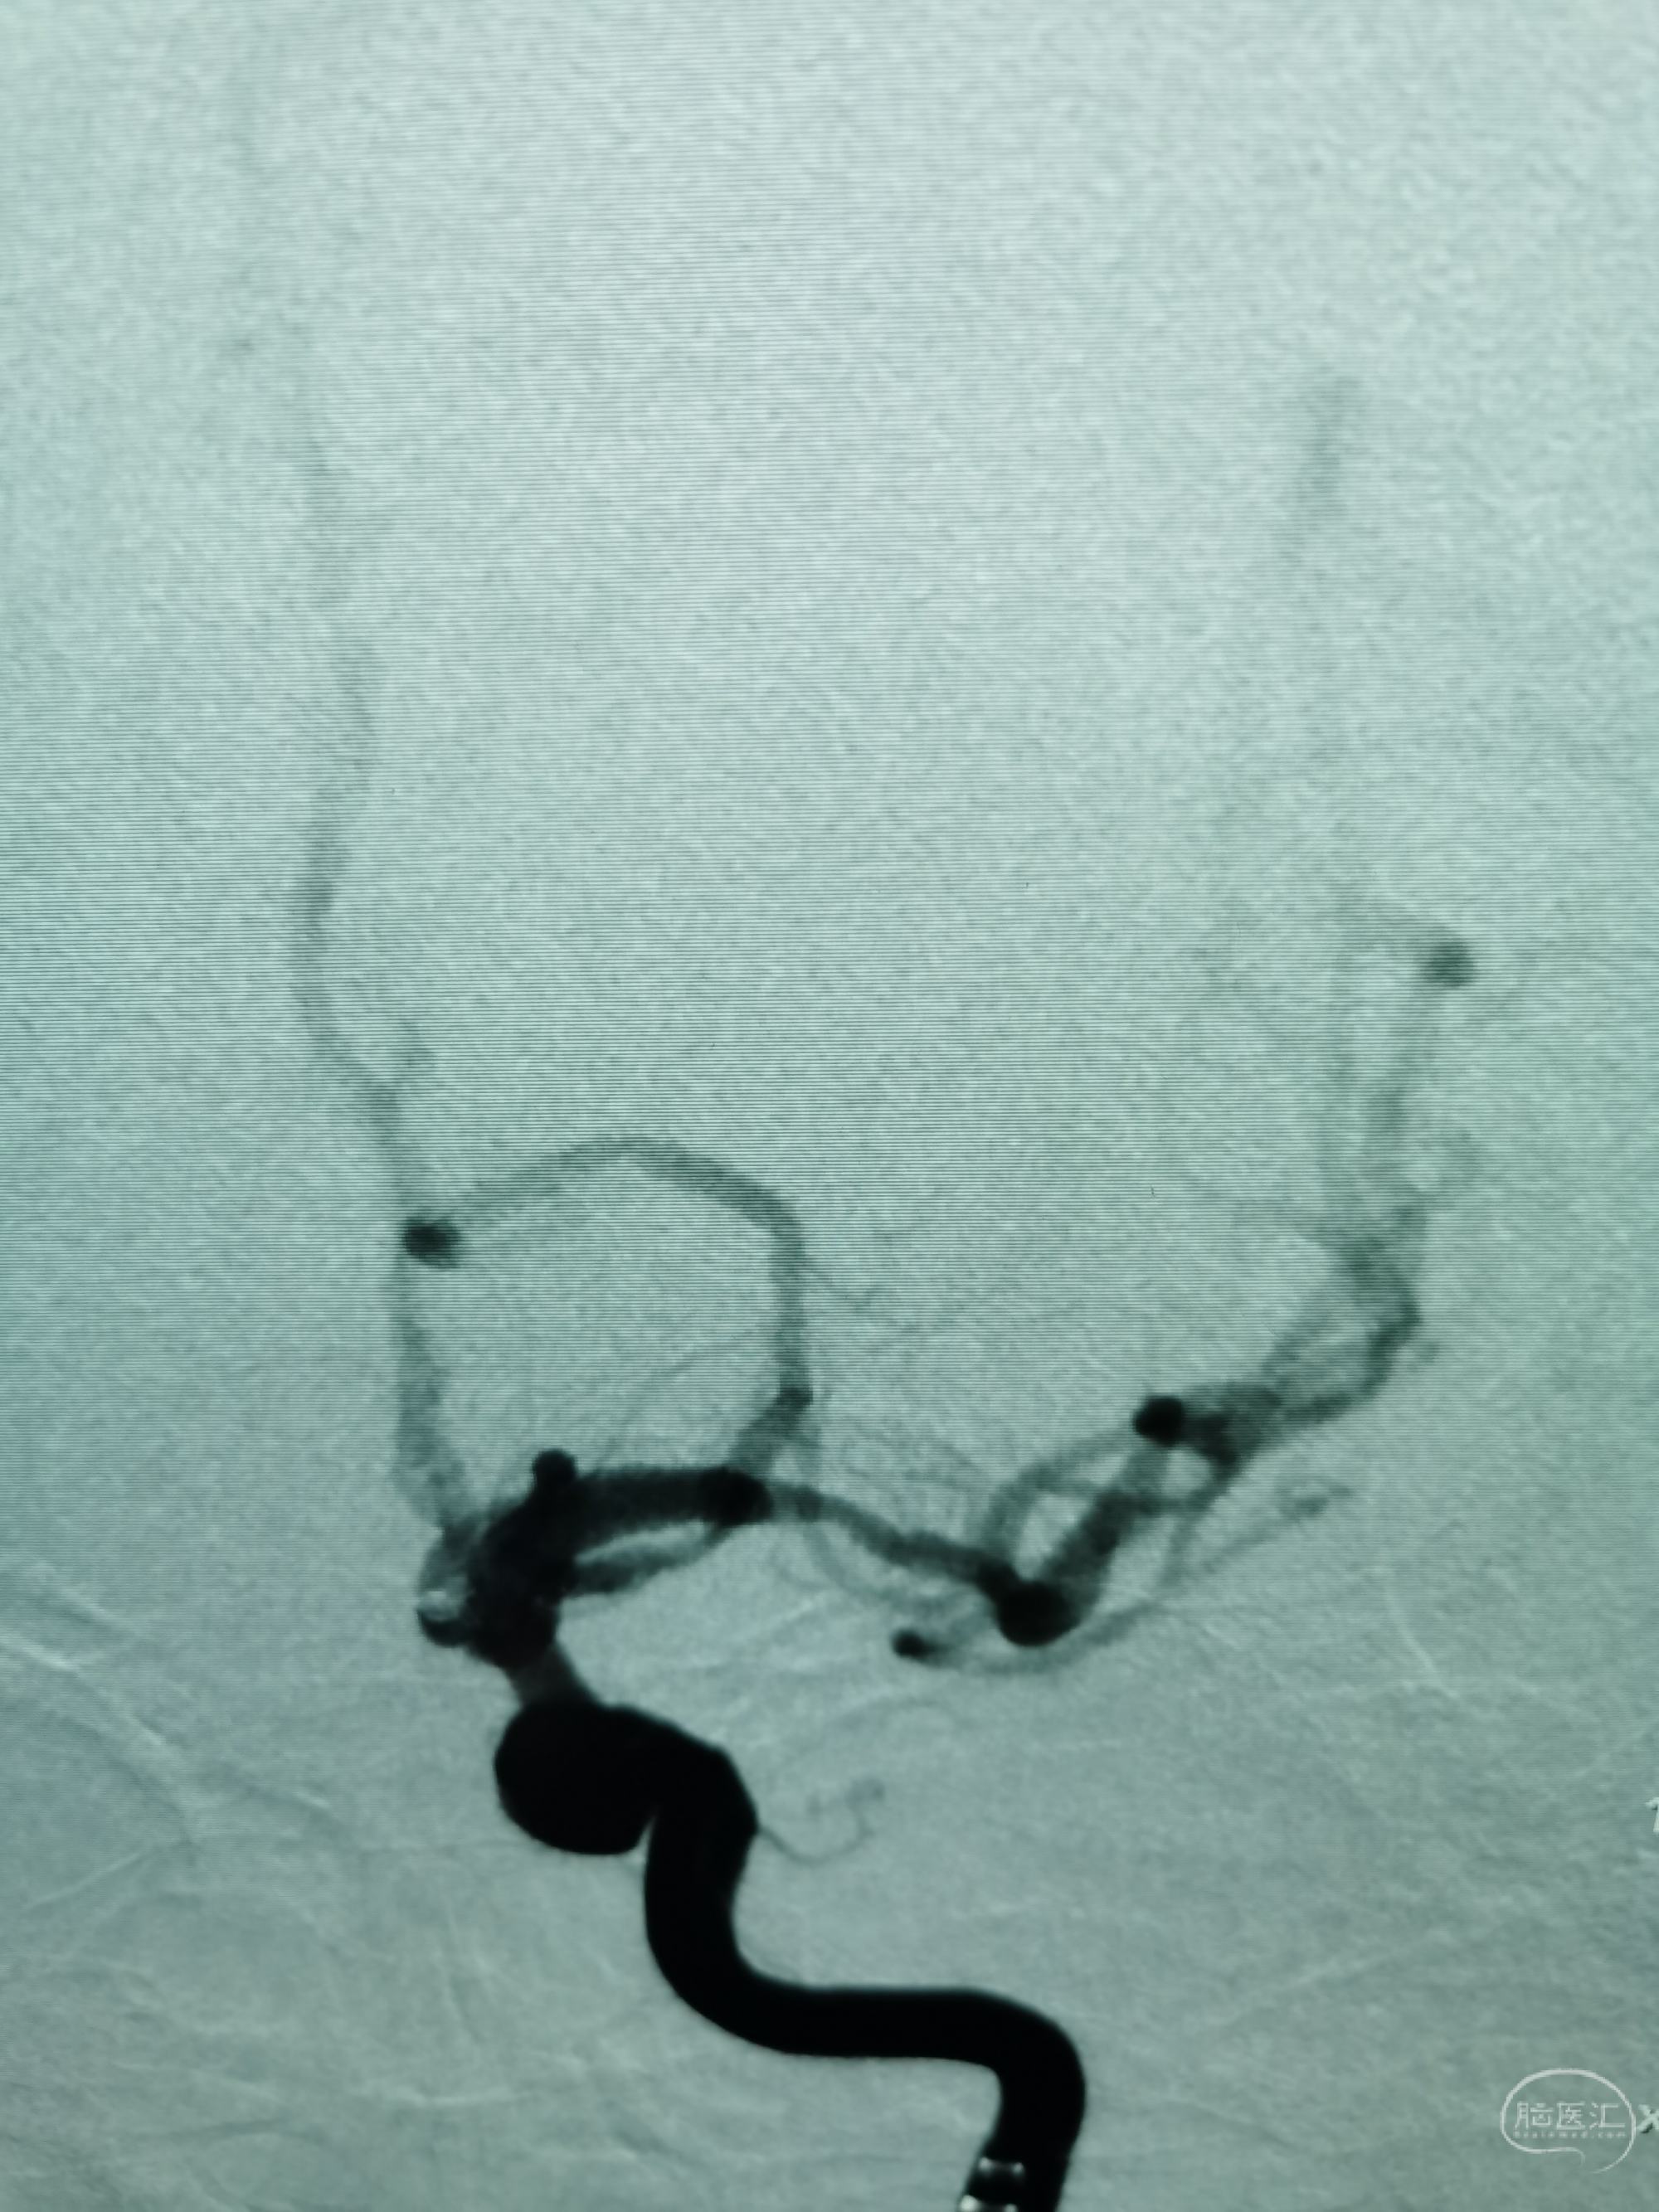

病例1 老年女性,蛛网膜下腔出血,SAH2级,诊断:左侧后交通动脉瘤。

头颅CT:蛛网膜下腔出血。

DSA示左侧后交通微小动脉瘤,起自后交通,血泡样。

3D示动脉瘤大小约1.36✘1.40mm

胚胎型后交通动脉。

压颈DSA造影示左侧P1缺如。